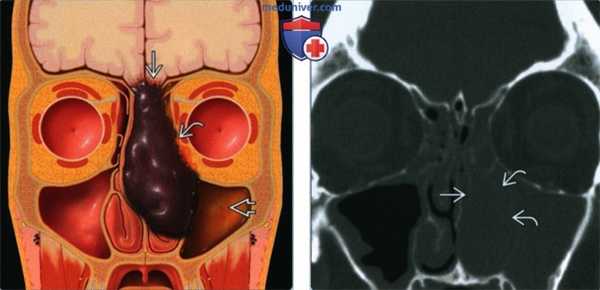

(Слева) На рисунке (поперечный срез) в полости носа показано темное, пигментированное (с высоким содержанием меланина) объемное образование. Определяется инвазия основания черепа, орбиты и латеральной стенки носа. Носовая перегородка смещена без признаков инвазии. В левой верхнечелюстной пазухе находится «запертый» секрет.

(Справа) При корональной костной КТ у пациента с обструкцией носа слева и носовым кровотечением визуализируется объемное образование в полости носа слева, обусловливающее эрозию средней левой носовой раковины и участков латеральной стенки носа.

2. КТ при синоназальной меланоме:

• Костная КТ:

о Дольчатое мягкотканное образование в полости носа

о Деструкция ± ремоделирование костей